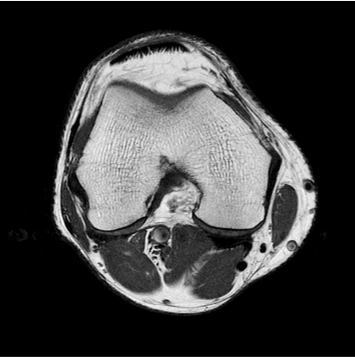

향상된 영상화질

향상된 대조도

노이즈 개선

모든 해부학적 부위 적용가능

IAI는 AI Deep learning을 통해 기존 장비의 촬영 프로토콜을 최적화합니다.

기존 프로토콜 대비 촬영 시간을 50% 단축시키며, 이미지 퀄리티는 증가합니다.